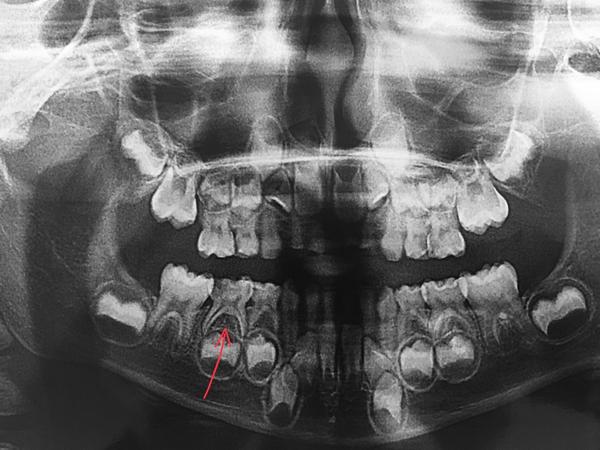

RTG vyzera takto. Dole oznaceny zub je vonku. Tie horne 6-tky + ostatne horne trvale co sa tlacia moze trvat este xy mesiacov kym sa to pohne, dovtedy co? 😓